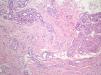

HistopatologíaSe tomó una biopsia en sacabocados de una de las lesiones. El estudio histológico mostraba una epidermis normal, mientras en la dermis media y profunda se observaba una proliferación desordenada de glándulas y ductos ecrinos maduros, con adipocitos maduros entremezclados (fig. 2). Además, se encontraron asociadas múltiples estructuras vasculares de paredes de grosor variable que resaltaban con la tinción inmunohistoquímica de CD31 (fig. 3).

Histopatológicamente el HAE se caracteriza por una proliferación de glándulas ecrinas maduras en la dermis media y profunda, en cercana asociación con canales angiomatosos dilatados o colapsados, de paredes finas y bien diferenciados. Algunas variantes histopatológicas incluyen también estructuras pilosas, glándulas apocrinas, focos lipomatosos, linfáticos y más raramente estructuras óseas5.